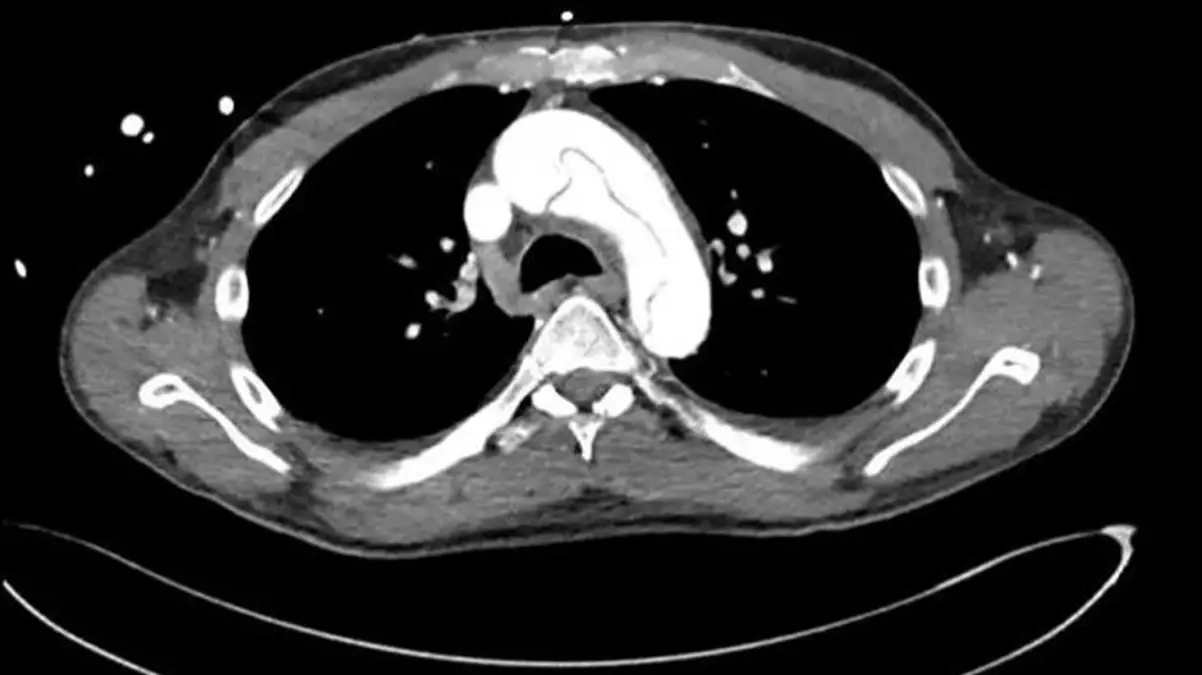

Hastaneye geldiğinde, aşırı düşük kan basıncı ve yavaş nabız tespit edildi. Ultrason taraması, aortun üst kısmında bir yırtık olduğunu gösterdi. Bu durum, acil açık kalp ameliyatı gerektiren hayati bir tehlike oluşturuyordu.

Hastaneye vardığında, doktorlar başlangıçta sepsisten şüphelendi. Ancak yapılan testler, aslında aort damarında bir yırtık olduğunu ortaya çıkardı. Bu durum, aort yetersizliği adı verilen ciddi bir kalp acil durumuna yol açtı.

Aort diseksiyonu olarak bilinen bu durum, genellikle göğüs veya sırtta keskin bir ağrı, nefes darlığı ve aşırı terleme gibi belirtilerle kendini gösterir. Ancak bu vakada, hasta bu tipik belirtilerin hiçbirini yaşamadı. Bu durum, vakayı daha da ilginç ve tehlikeli hale getirdi.